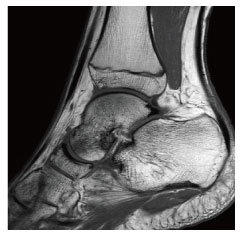

当院のMRI画像集